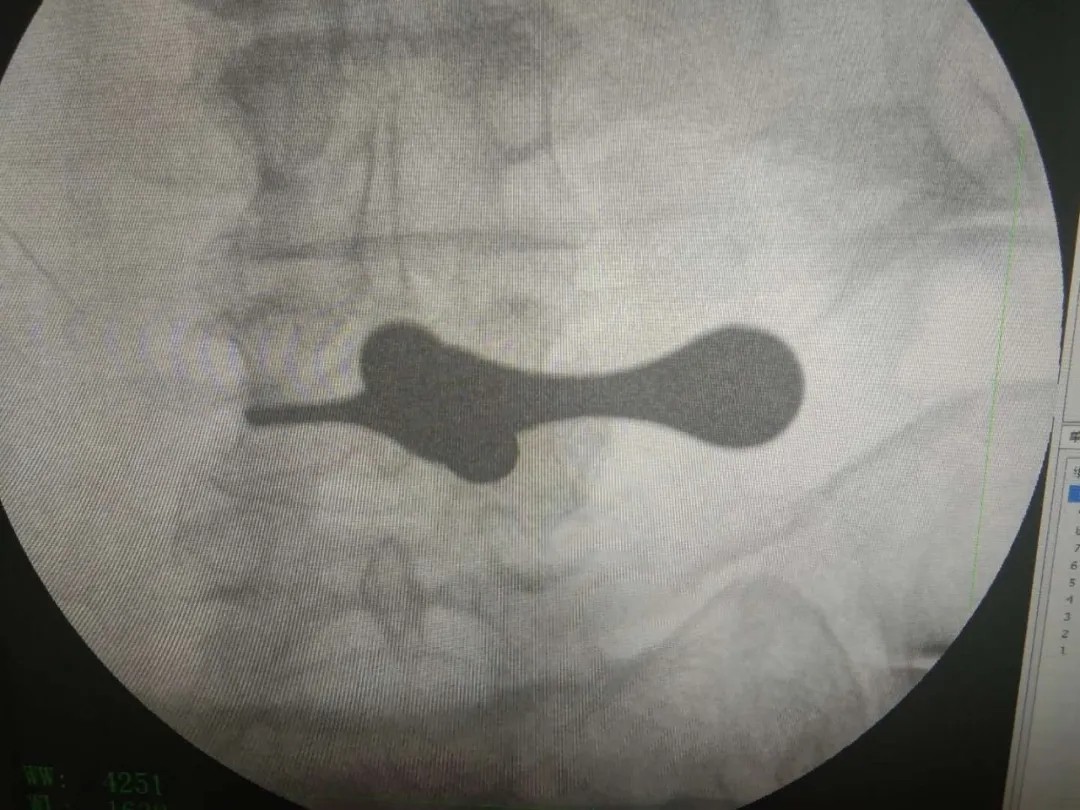

术后影像:

椎间孔镜技术,是一种方兴未艾的微创手术方法,在治疗椎间盘突出、腰椎管狭窄症等治疗中常见常用。于治强主任这两个病例采用椎间孔镜技术治疗,取得相当不错的疗效。